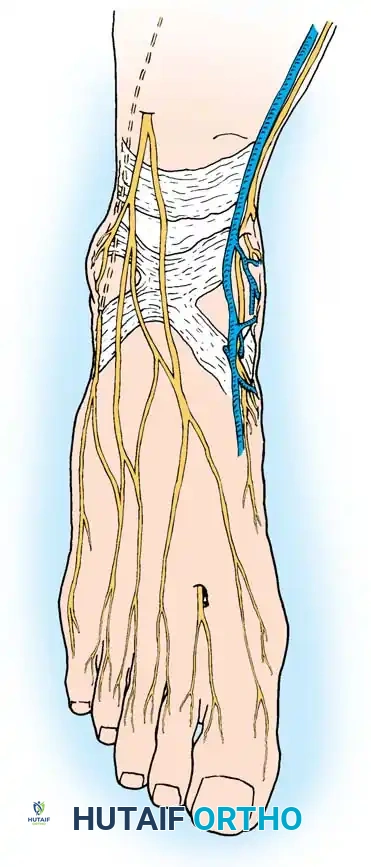

• With the patient supine and a tourniquet on the limb, extend a midline, straight, medial incision from the middle of the proximal phalanx to 2 cm proximal to the junction of the medial eminence with the metatarsal shaft (Fig. 78-13). This incision usually is in an internervous plane between the most medial branches of the superfi cial peroneal nerve dorsally and the medial proper digital branch of the medial plantar nerve plantarward. (McBride recommended a single incision beginning at the fi rst web space and extending proximally and medially across the metatarsal, ending on the medial side of the fi rst metatarsal proximal to the exostosis.)

• Begin the second stage with a dorsal longitudinal incision beginning 2 to 3 mm proximal to the dorsal aspect of the fi rst web space to avoid web contracture postoperatively; extend it proximally between the fi rst and second metatarsal heads for 3 to 4 cm (Fig. 78-18). This allows adequate exposure of the adductor insertion into the base of the proximal phalanx, the lateral head of the fl exor hallucis brevis muscle converging on the fi bular sesamoid, and the entire lateral capsule from the extensor hallucis longus muscle to the plantar plate.

• Delicate retraction of the skin exposes the dorsal digital branches of the veins, which should be cauterized if they obscure the deeper dissection. The terminal branches of the fi rst dorsal intermetatarsal artery may be encountered at a location adjacent

Modifi ed McBride Bunionectomy TECHNIQUE 78-1—cont’d to the proper digital branches of the deep peroneal nerve to the fi rst web space.

• This deep transverse intermetatarsal ligament, which lies just plantar to the adductor, may be released by the incision along the lateral border of the sesamoid. If not, release this ligament, carefully preserving the neurovascular bundle immediately beneath it, and incise the lateral capsule. Mann emphasized that release of the deep transverse metatarsal ligament endangers the neurovascular bundle to the fi rst web space, which lies immediately beneath this ligament. Sliding a small Freer elevator between this ligament and the neurovascular bundle would protect the latter structures.